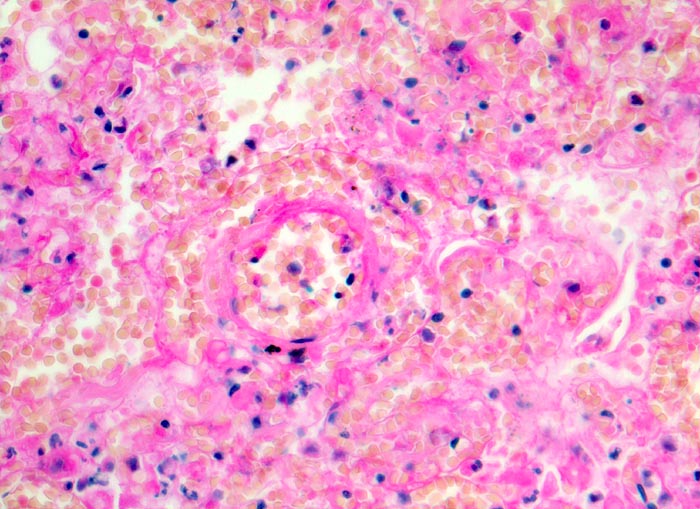

• Pulmonalarterienast mit nicht wandhaftendem Thrombembolus am Rand des Infarktes.

• Frischblut im Lumen des begleitenden Bronchiolus.

• Pulmonalarterienast mit Strickleiter.